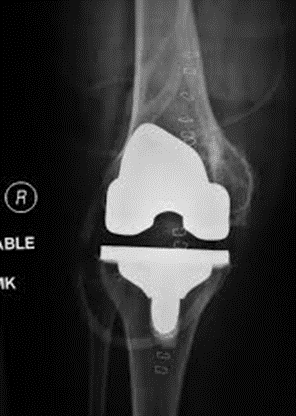

Your Implants

We use the MAKO robotic knee replacement platform to perform your surgery. It allows us to accurately plan the position of your implants.

The implants used are made by Stryker, and are called the Triathlon. They have a long clinical history of success. They are either fixed to your bone using bone cement, or are designed to grow into your bone over a period of several weeks. The decision for this is based on your bone quality at the time of surgery. The components are made of cobalt chrome and titanium.

Follow Up Appointments

You will be seen at 2 and 6 weeks post operatively

We will get x-rays to ensure the implants are in an appropriate position, and check your wound to ensure proper healing. We will also check your limb for any signs of blood clot, and ensure you are achieving your range of motion goals. Long term, we will follow you on an annual basis to ensure the components maintain their position and there are no signs of implant failure.